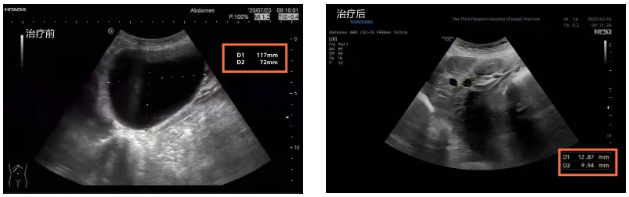

原来,80岁的李婆婆在一年前频繁出现右上腹胀痛不适,为了查明原因,李婆婆来到了91porn (湖北省中山医院)中西医结合肝病科就诊。完善检查后结果提示,婆婆的肝脏上长了一个11.8cm×7.2cm的巨大囊肿,这也是其右上腹胀痛以及转氨酶升高,肝功能异常的主要原因。

消除顾虑后的李婆婆欣然接受了治疗,术后囊肿缩小到1.3cm×1.0cm,治疗后为了防止囊肿复发,刘黎明主任根据李婆婆的体质应用中药辩证施治,术后随访1年,囊肿持续缩小,原本巨大的囊肿变得只有花生米大小,肝功能也恢复正常,于是就出现了开头的一幕。